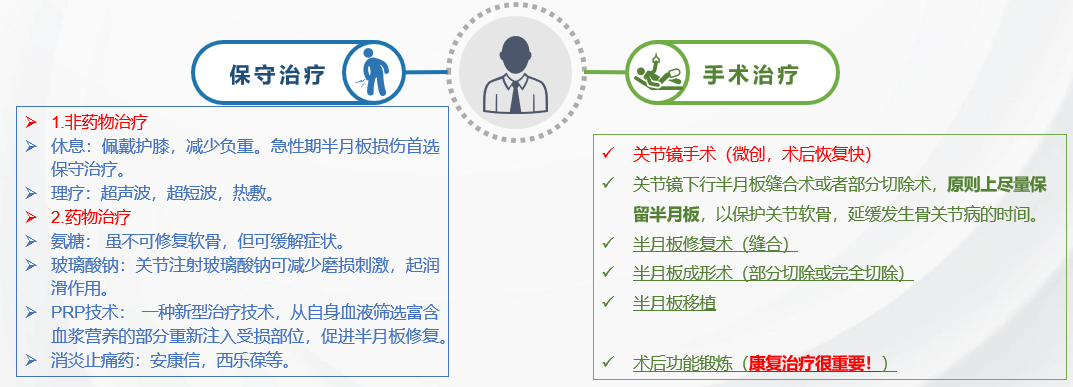

【半月板损伤的治疗】

半月板损伤的治疗